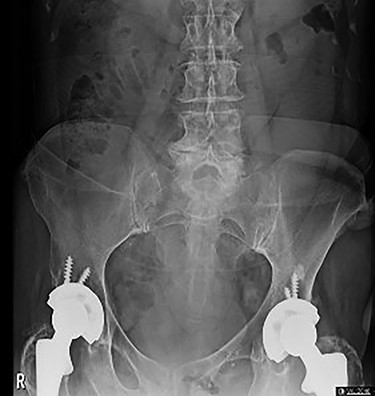

On initial presentation, her blood results were as follows: white cell count (WCC) 14.8 × 109 cells/l (RR 4.3–11.2 cells/l), neutrophils 12.3 × 109 cells/l (RR 2.1–7.4 cells/l) and C-reactive protein (CRP) 1.9 mg/l (RR 0–5 mg/l). Imaging performed included an abdominal film, which showed nonspecific bowel gas pattern (Fig. 1). The patient was managed conservatively and discharged home. She represented 2 days later with worsening symptoms and blood results of WCC 20.1, neutrophils 18.4 and CRP 6. She was admitted under the surgical team and a thoracic and abdominal CT scan was done (Figs 2–4). It was initially reported as significant dilated small bowel loops in keeping with small bowel obstruction due to a femoral hernia. However, the scan was revisited by the surgical team in more detail as the images appeared to represent an obturator hernia. Upon further discussion, these findings were corroborated by the radiologist and a strangulated left obturator hernia was identified.